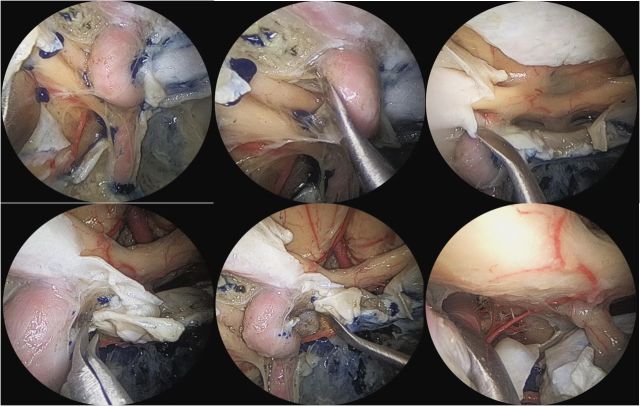

坐位听神经瘤切除术视频(摘自鲍教授上述讲课)

鲍遇海教授:坐位听神经瘤切除术